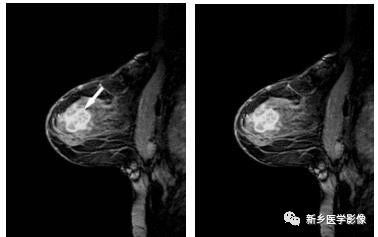

乳腺癌的MRI增强图像

左乳MRI矢状位,呈边缘环状强化向中心渗透,呈向心样强化(白箭)

MRl对肿块的分析与X线片有相似之处。平扫检查,病灶形态不规则,呈星芒状或蟹足样,边缘不清晰或呈毛刺样为恶性病变;反之,形态规则,边缘清晰则提示为良性。但少数病变和小的病变可表现不典型。平扫T1WI上肿块多呈中低信号;T2WI上肿块信号各异;纤维成分含量多的肿块呈中信号低,细胞及含水量多的肿块呈高信号。一般良性病变内部信号强度多较均匀;恶性病变内部可有液化、坏死、囊变或纤维化,甚至出血,可表现为高中低混杂信号。

动态增强检查恶性病变强化不均匀或呈边缘强化,强化方式亦多由边缘环状强化向中心渗透,呈向心样强化;而良性病变的强化多均匀一致或呈弥漫性斑片样强化,部分病变的强化方式由中心向外围扩散,而呈离心样强化。动态增强血流动力学表现:通常乳腺恶性病变增强后信号强度趋向快速明显增高且快速下降;而良性病变则表现为延缓的均匀强化或渐进性强化,病变的信号强度在增强晚期仍具有上升趋势。